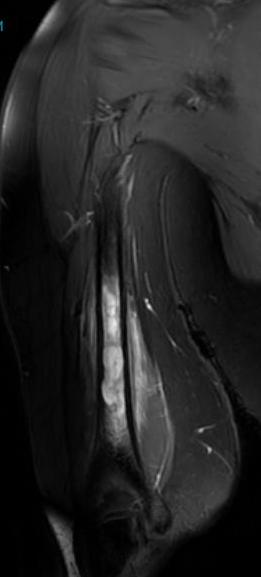

MRI

Low signal intensity of T1 / high signal intensity on T2

- intramedullary extent

- skip lesions

Significant soft tissue mass with significant edema

Ewing's humerus

Ewing's femoral diaphysis, subtle on xray with large soft tissue component